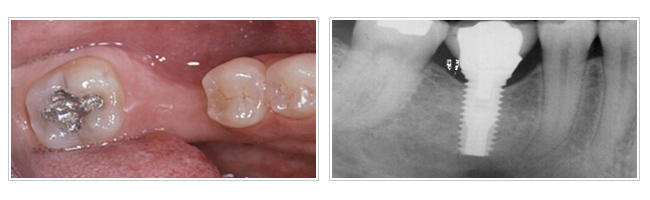

如何進行「人工植牙」治療?

人工植牙是屬於高科技與醫學先進的結晶,使用與人體骨質相容性高的醫學用鈦金屬材料製成,因此鈦金屬與牙床骨緊密結合,在正常的情況下須3~8個月(下顎須3~6個月,上顎須6~8個月)才能做第二階段的工作,即裝上固定假牙。

人工植牙完成後如何做維護?

任何義齒完成後,都需有良好的口腔衛生保養,人工植牙與自然牙一樣,需要使用牙刷、牙線及口腔清潔用品來清潔及定期口腔檢查,良好的咀嚼習慣便能延長您的人工牙根的壽命。